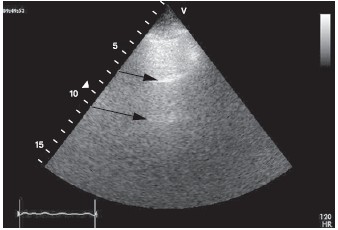

Отек легких. При отеке легких у больных острым ИМ частота летальных исходов в течение месяца достигает 20—40% даже в эру фибринолиза [11]. У больных с острой левожелудочковой недостаточностью (отеком легких) при УЗИ легких наблюдается появление множественных УЗ-артефактов по типу хвоста кометы от поверхности легких. В норме при УЗИ легких вследствие реверберации с определенной периодичностью наблюдаются одна или две преимущественно горизонтальные параллельные линии, расположенные позади плевры (рис. 5).

Ультразвуковое исследование легких в норме. Регистрируются горизонтально расположенные реверберационные сигналы (стрелки).